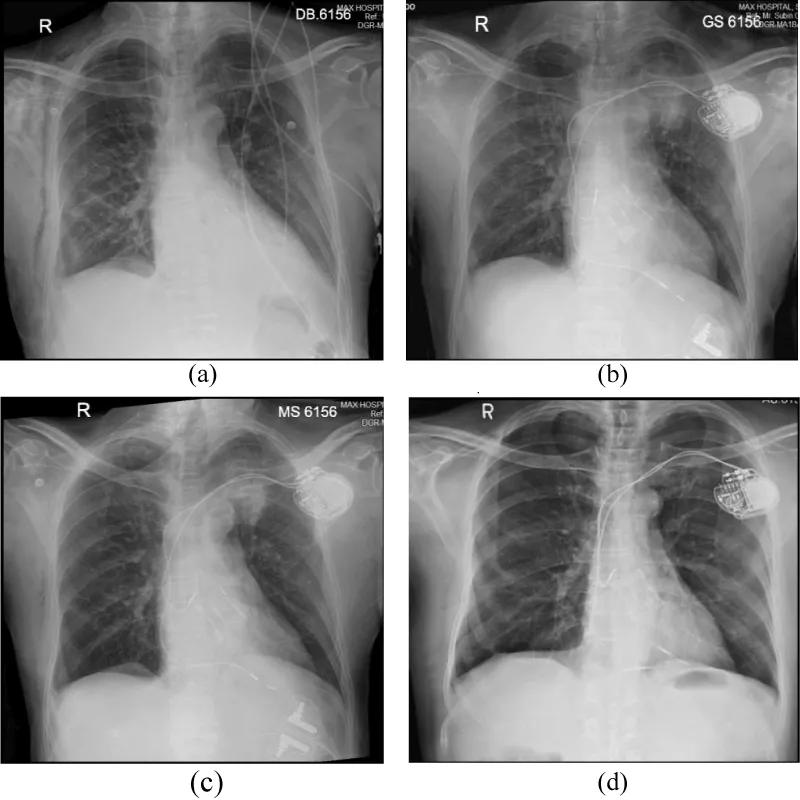

A 65-year-old man was admitted to our hospital with severe aortic stenosis for aortic valve replacement. He underwent aortic valve replacement with (#25/27 mm) XL sorin perceveal sutureless aortic valve prosthesis (bioprosthesis). Following the procedure, he developed high grade AV block which did not improve on two weeks; hence he was planned for a permanent dual chamber (DDD) pacemaker implantation. He was on low molecular heparin (enoxaparin 0.6 ml subcutaneous twice a day) and received the last dose of enoxaparin the last evening before the pacemaker implantation. However, he had a normal haemoglobin, platelet count and his INR was 1.1. His pre-procedure chest x-ray had normal lung parenchyma (Figure 1a).

Figure 1: (a) Pre procedure chest x-ray, (b) Immediate post procedure x-ray showing alveolar haemorrhage, (c) post procedure x-ray after one day showing clearance of lung parenchyma; (d)post procedure x-ray after 72 hours showing almost complete normalization.

However, immediate post procedure chest x-ray showed left upper lobe homogenous opacities suggestive of alveolar haemorrhage with no evidence of pneumothorax (Figure 1b). We initially planned for a CT scan of thorax, but he improved and had no significant hemoptysis after the initial bout of hemoptysis in the Cath-lab. There was no drop in hemoglobin or no documented episode of hypoxia either. His subsequent chest x-rays showed clearance of the opacities (Figure 1c) and finally at fourth post procedure day, he was started on oral anticoagulation, chest x-ray became normal (Figure 1d) and he was discharged.